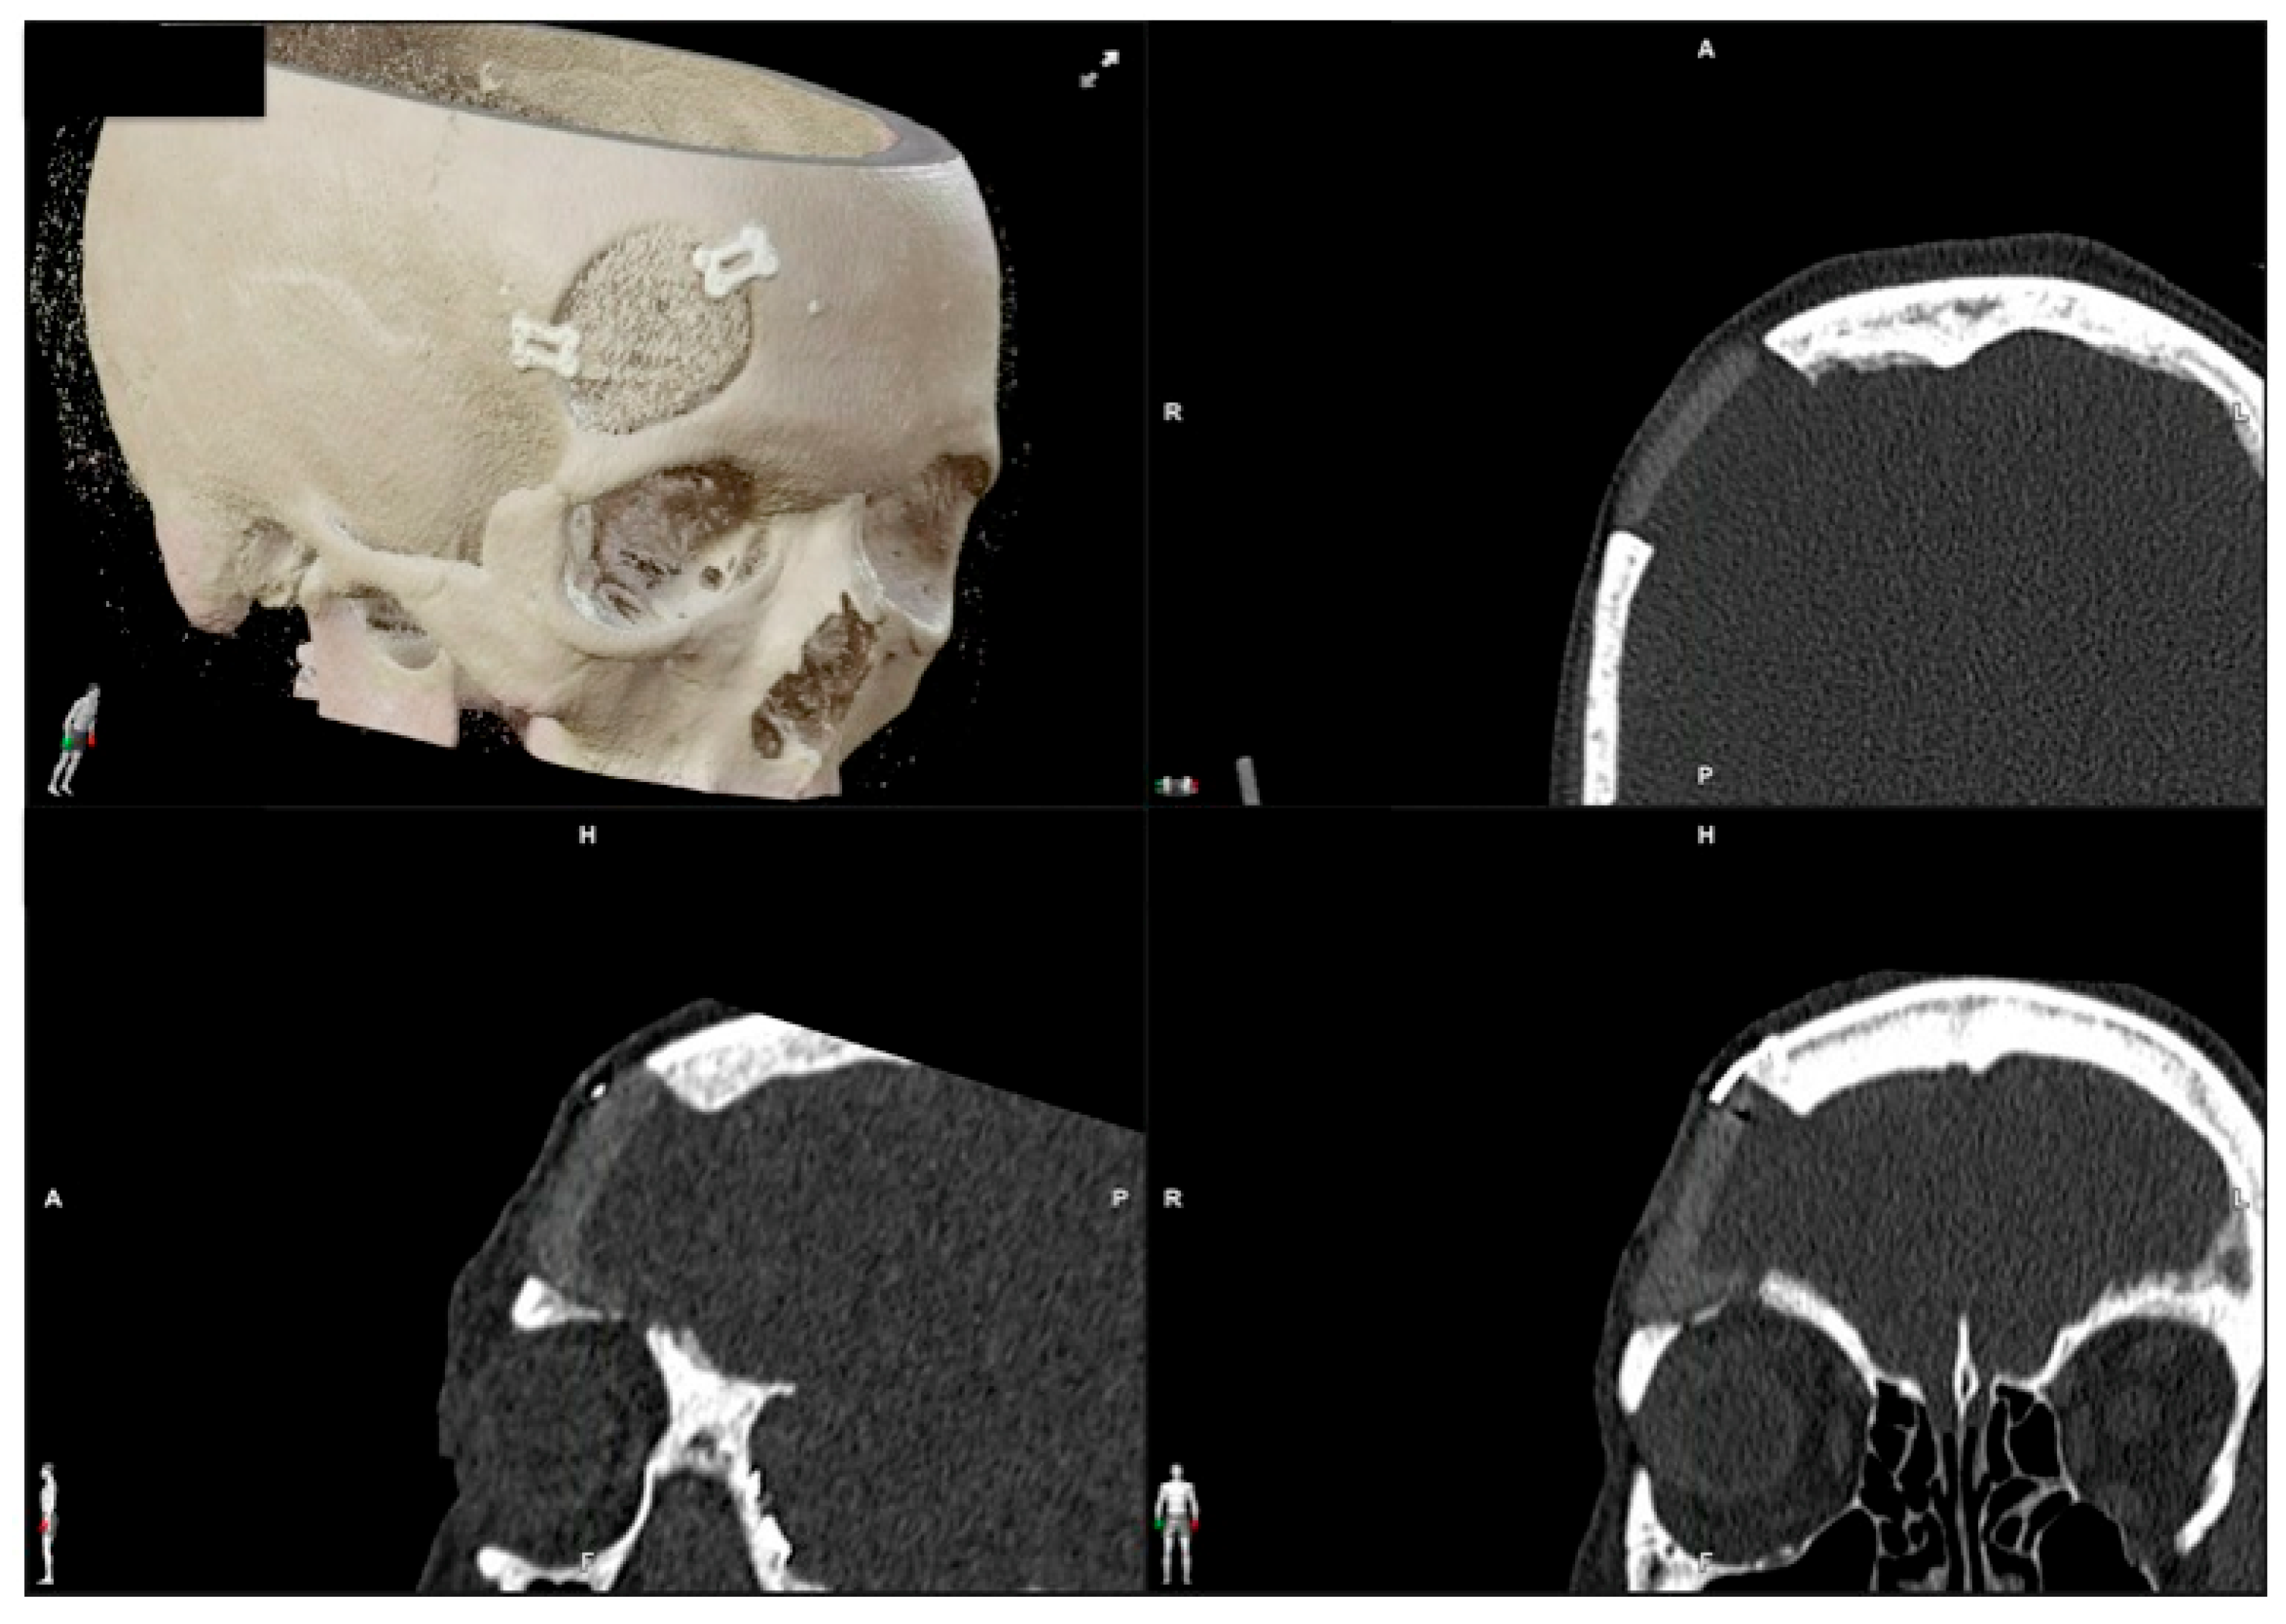

| 1 | 53/F | L/25 mm | Y | 4 mo | Dystopia | N | CT, MRI | Supraorbital rim, orbital roof | Intraosseous venous malformation | - | Resection + reconstruction | Y | Y | 1st, 2nd, 3rd | Coronal | Y | Piezoelectric device | N | PEEK prosthesis | 7 y/N |

| 2 | 54/F | R/33 mm | Y | 9 y | N | Y | CT, MRI | Frontal bone, orbital roof | Intraosseous venous malformation | - | Resection + reconstruction | Y | Y | 1st, 2nd, 3rd | Coronal | Y | Piezoelectric device | N | PEEK prosthesis | 6 y/N |